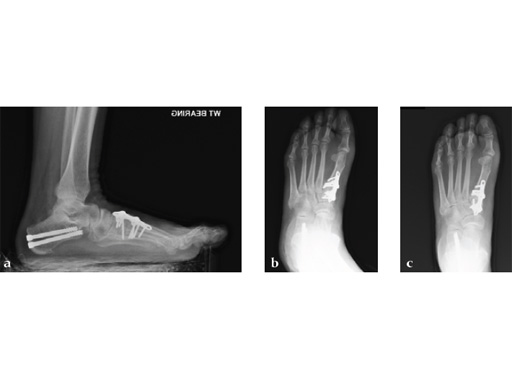

Case 5: First TMT, straight fusion and TMT fusion plates

A 46-year-old obese woman with coronary artery disease had sustained a Lisfranc injury while performing an exercise program. She was unable to weight bear and used an electric scooter.

In an effort to restore her ability to exercise and taking into consideration her body weight and upper extremity weakness, a decision was made to use the variable angle locking compression plate. These postoperative x-rays were obtained at 3 months, one month after beginning weight bearing. The patients pain was reduced and she was able to resume a progressive exercise program after 4 months following surgery.

Case provided by Michael Castro, Scottsdale, Arizona